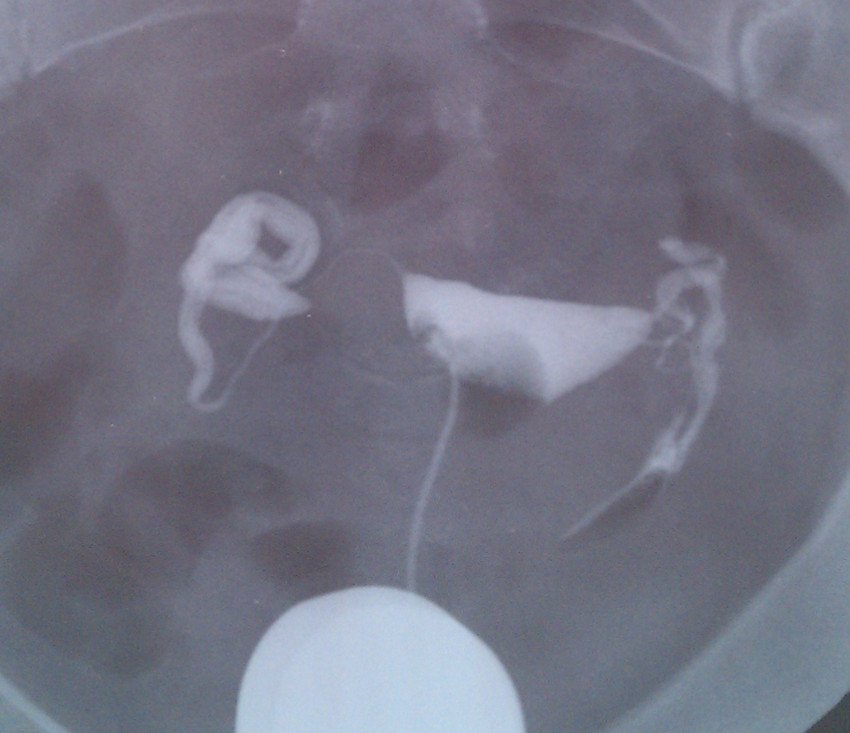

做的输卵管造影的片子,结果报告医生是手写的,看不懂写了什么 请帮我看写这个造影片子,输卵管通还是不 通,是不是有粘连?谢谢了 点击展开 匿名用户 2014-05-21 10:55 为您推荐: 其他回答 病情分析: 你好很高兴为你解答通过你的图片看好像是有一次堵住了有一次还可以 指导意见: 通过你的图片看应该有一次的输卵管儿堵住了,另一侧应该还可以通卡希望我的回答对你有所帮助谢谢! 匿名用户 2014-05-21 11:43 相关问题 做完造影报告单上写的输卵管通而不畅,但医生看片子说还好,是怎么回事啊? 7 6号来的姨妈,7 11干净,7 14做了输卵管X造影,8 6 末次姨妈,确定怀孕,但是,医生 昨天上午做的妇科TCT检查,医生说今明两晚就会排卵让这个月试孕,如果不孕下月做输卵管造影,请问今晚